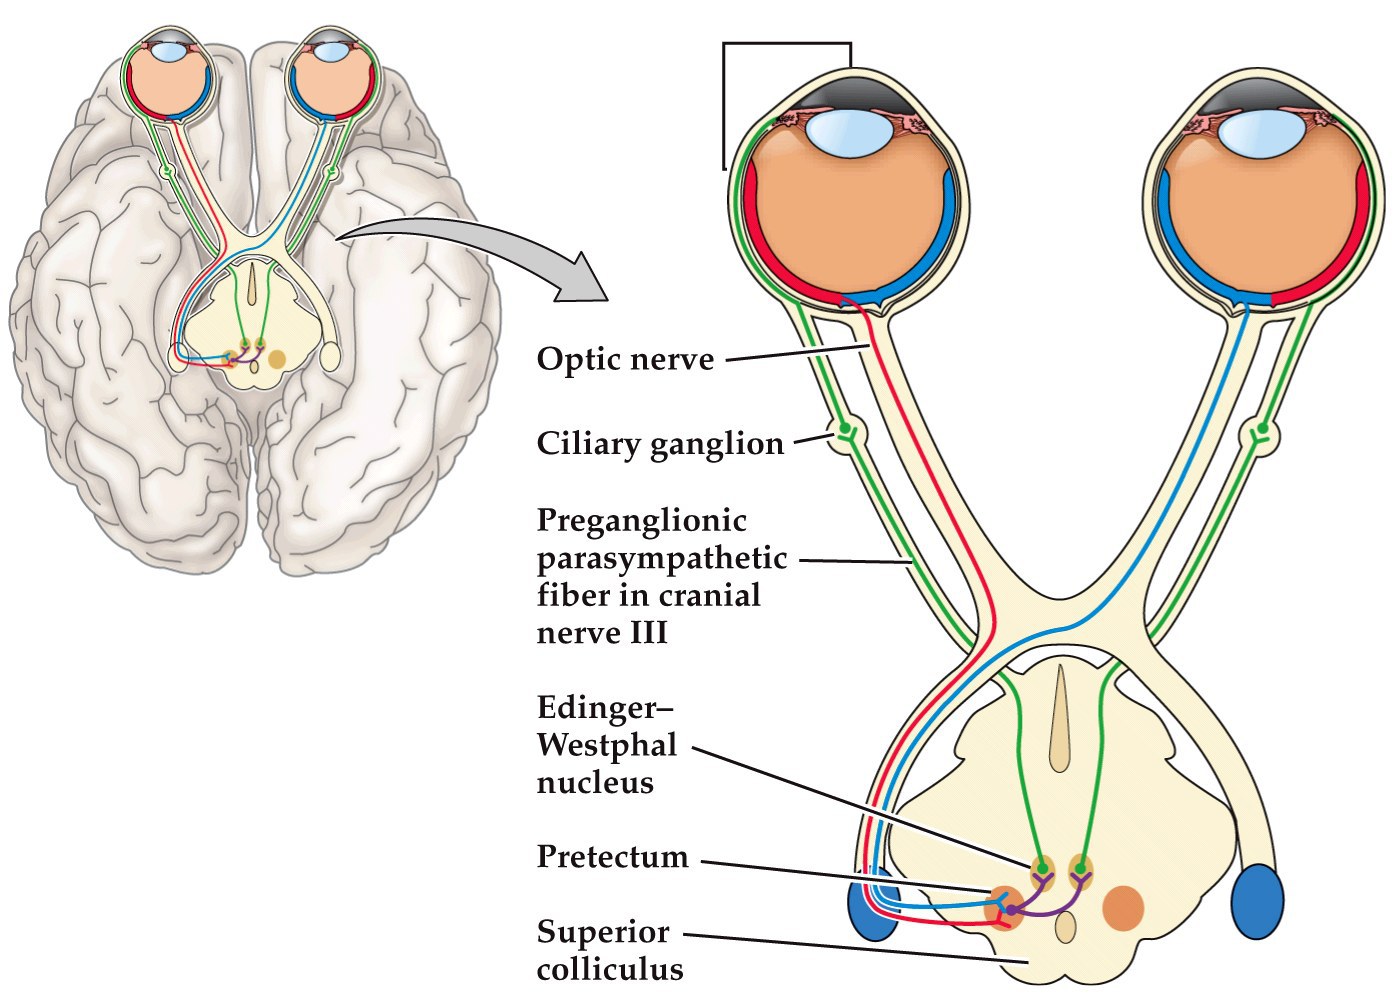

The pupillary light reflex

- Light hits retina, sends out axons to both sides of brain that go to the pretectum

- Pretectal neurons project to contra- AND ipsi-lateral Edinger-Westphal nuclei (in midbrain)

- Edinger-Westphal nucleus projects to the ciliary ganglion (PNS)

- Ciliary ganglion projects to the constrictor muscle in the iris. Shining light in one eye leads to constriction of both eye’s muscles

Circuitry responsible for the pupillary light reflex

- Question: Where is the site of injury if shining a light into the left eye causes both eyes to constrict but shining light into the right eye does not cause either eye to constrict?

- right optic nerve

answer: right optic nerve